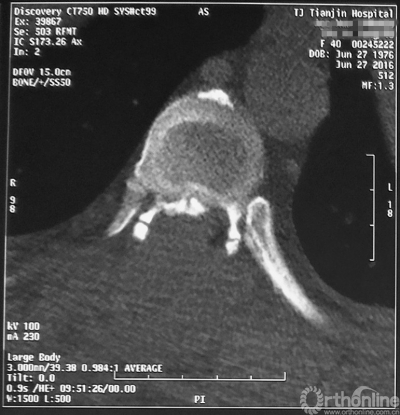

术后CT

最终,由任万陆主任亲自为患者进行了全身麻醉,苗军主任为其实施了后路的胸8-10椎板减压术,手术麻醉过程平稳,手术出血不多,术后不仅没有截瘫,神经功能进一步恢复,好转出院。术后一个月随访,患者已经可以扶助行器行走,患者对疗效非常满意。